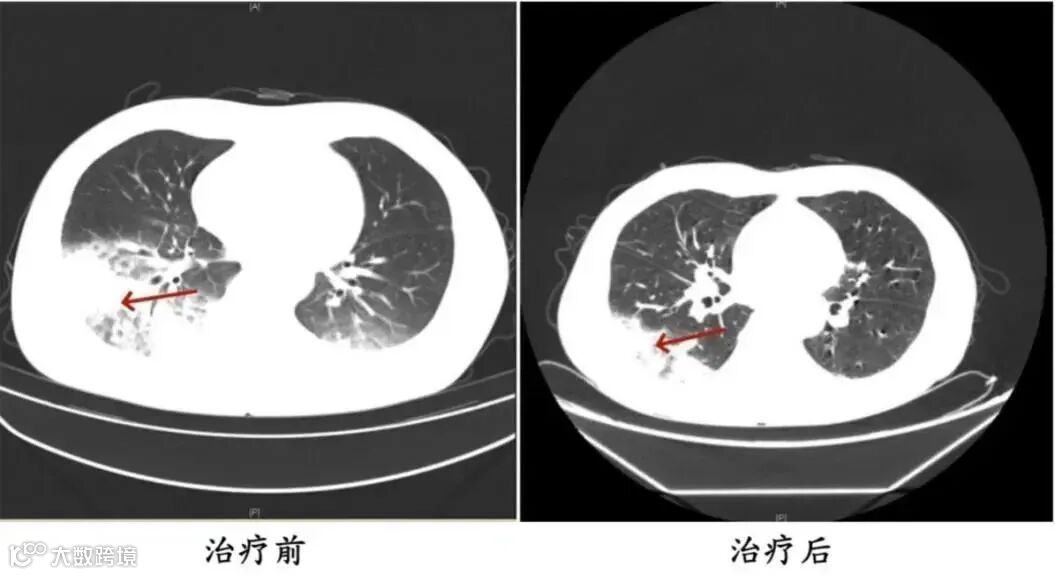

胸部CT显示李先生的左肺已出现大面积白色影像,几乎占据一半肺部。经过肺泡灌洗NGS检测,最终确认“罪魁祸首”是嗜肺军团菌。

李先生肺部治疗前与治疗后的对比